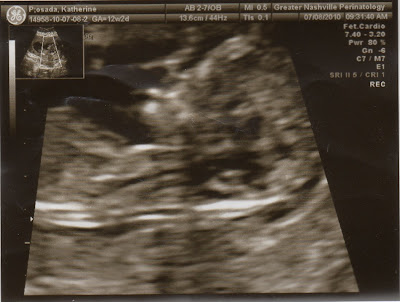

Sonogram photos of my baby sister!

We found out that the baby is going to be a girl! Here are some photos of her that the doctor took.

7/8/10:

(This is how the doctor knows she is a girl!)